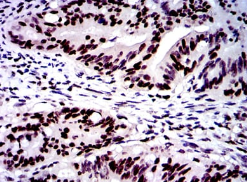

IHC    1/200 - 1/1000